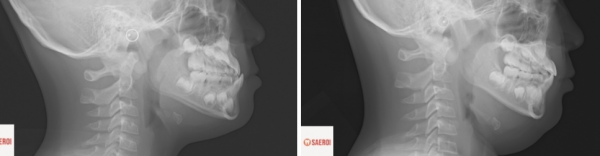

측면 엑스레이에서는

거꾸로 물리는 앞니가 명확히 관찰됨과 동시에

위턱의 저성장과 아래턱의 과성장으로 인해 발현된

주걱턱 모습을 확인할 수 있습니다.

왼쪽이 교정 전 오른쪽이 교정 후입니다.

측면 엑스레이 상에서도

위 앞니가 아래 앞니를

정상적으로 덮게 됨을 볼 수 있고

이 과정에서 앞니의 각도가

정상으로 바뀌게 되었습니다.

코 옆면인 중안면의 뼈가 전방으로 성장 촉진되면서

얼굴의 볼륨감이 살아나게 되었습니다.